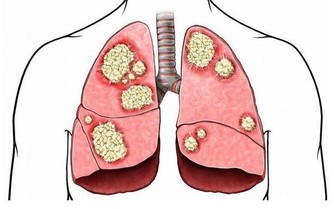

腫瘤科醫生不希望你:發霉食物還要吃

花生、玉米、黃豆、堅果等食物如果發霉了,

其可能產生的黃曲霉毒素會危害人體健康,長期食用的話,更會增加致病風險。

吃霉變食物最容易犯癌,而且,水洗和高溫烹調也難以將其破壞,一定不要再吃了!